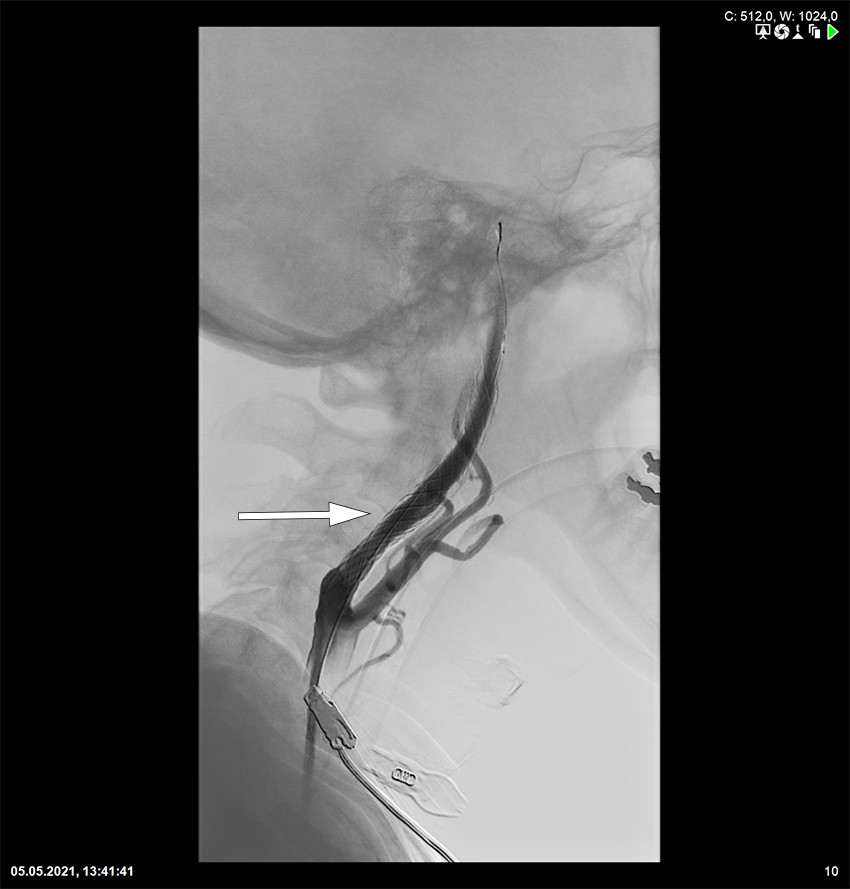

Tandemokklusjoner er spesielt utfordrende både teknisk sett og med tanke på en nødvendig bruk av antitrombotiske medikamenter for å holde stenten åpen. Pasientene vil som regel behandles med carotisstent kombinert med trombektomi (figur 3). Okklusjoner og stenoser i a. basilaris og a. cerebri media kan også ved indikasjon stentbehandles (22).